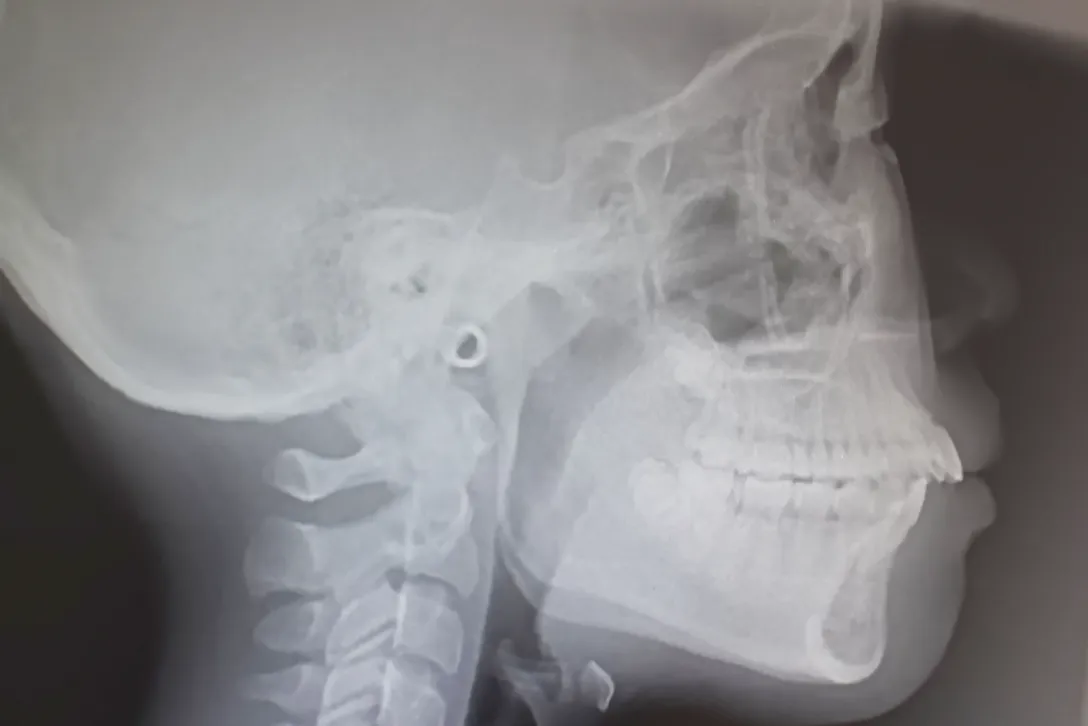

正確な診断と治療計画の立案のために、レントゲン撮影や歯科用CT、歯型の採取など、矯正治療に必要な精密検査を行います。

歯や顎の骨の状態、噛み合わせのバランスなどを立体的に把握し、お一人おひとりに最適な治療方針を組み立てていきます。